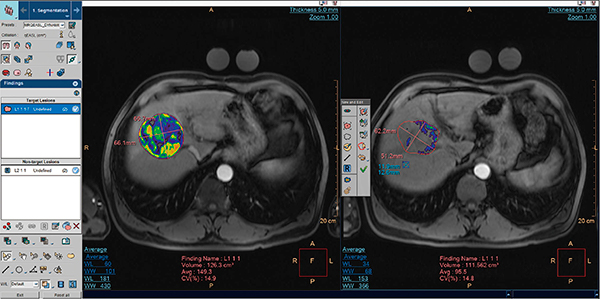

●MRI用アプリケーション “MMTT qEASL”

マルチモダリティ腫瘍トラッキング(MMTT)は,経時変化の可視化を目的とした,腹部系疾患に有用なマルチモダリティアプリケーションである。MMTTアプリケーションは,マルチモダリティのCT,MRI,PET/CT,SPECT/CTスキャンにおいて,解剖学的画像および機能画像を表示,処理,分析,定量化,操作することを目的としている。MMTTアプリケーションでは,1つまたは複数のスタディの時間的経過(複数の時間ポイント)において,イメージング,セグメンテーションと測定,ならびに腫瘍やリンパ節といった腫瘍病変の定量的かつ特性を示す情報が得られる。また,“qEASL(quantitative European Association for the Study of the Liver)”は,スキャンを高度に対比し,非造影との比較に基づいて,肝がん(EASL)用に最適化された基準が得られる。当社は,さらに3D(容積)測定を含め,ccを単位とする腫瘍容積の定量的な結果を提供し,総腫瘍体積の割合として示すことができる(図2)。

図2 MMTT qEASL